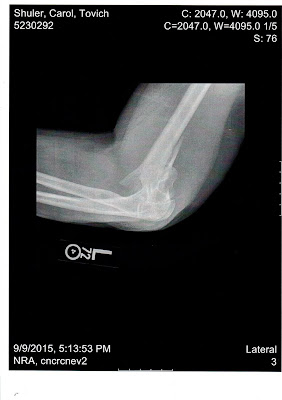

X-ray of Carol Shuler's shattered arm, broken by a Missouri deputy. This image, taken before any repair efforts, shows that the force was so violent that the humerus (the large bone in the upper arm) almost was forced through the skin. This is X-ray No. 2 of three showing the injury before treatment.

(X-ray from Cox North Medical Center, Springfield, MO.)

Carol was trying to enter our apartment to retrieve some of our belongings, as she had been told she could do. Specifically, she was trying to get our cat's litter box and was headed to the front door for that purpose, when a deputy jumped her. I saw the whole thing from about 15 feet away, while seated in the driver's seat of our automobile, which was parked in the driveway. Arnott saw it from a vantage point about 10 feet closer than mine. And what was the sheriff's immediate reaction to seeing one of his deputies brutalizing a 55-year-old woman who was trying to get her cat's "latrine"? Arnott's response was to lie. He pointed at Carol and said, "She assaulted a police officer." That statement is absurd to anyone who witnessed the event. And it's even more absurd when you consider that Carol wound up with a severely broken arm that required surgery, and there is no indication that any of the half dozen or so officers on hand--armed with at least one assault rifle and numerous handguns--suffered the slightest scratch. How badly was Carol's arm broken? The image above is the second of three X-rays we received of her original injury, before any repair was attempted. The break is so severe that . . . well, I get both sick and outraged just looking at it. Why have we been slow to bring these images to you? Well, that's largely because Carol was in custody when they were taken. Yes, you heard that right--with her arm broken as you see above, she was handcuffed (both arms twisted behind her), thrown in the back of a cruiser and transported to the Greene County Jail. Because of Arnott's lying eyes--and lying tongue--she apparently was going to be charged with assaulting a police officer. The deputy who drove her to the jail told her she was facing a felony and likely a $100,000 bond. At some point, Carol (likely in shock; she would receive treatment with oxygen) announced that her arm was killing her. Someone finally took notice, decided this might be serious, and had her transported to Cox North Medical Center, a few blocks from the jail. Most of Springfield's modern medical facilities--including Cox South (where Carol eventually had surgery)--is on the city's southside, in an area known as "The Medical Mile." Cox North, which dates to 1906, is a remnant of the city's medical past. When I was growing up here in the 1960s and '70s, Cox North was known as Burge Hospital. The facility now is used mostly for psychiatric services, but it does have X-ray equipment. And after seeing images produced at Cox North, it didn't take a knowledgeable medical person long to say, "This woman's arm is broken, badly." News must have gotten to Arnott in a hurry because Carol was taken to Cox South to have her arm set and get scheduled for trauma surgery. At some point, Arnott must have decided that Carol didn't assault anyone after all--and bringing bogus charges against her might make his department look even worse than it already was looking. At any rate, we haven't heard anymore about charges against Carol. As for charges against the officer, that might be another story. It looks like Ben Fields, the school-resource officer who was fired in Richland County, South Carolina, after body slamming a 16-year-old female student and dragging her across a classroom, might face criminal charges for assault--and it appears, thankfully, that the student sustained no serious injuries. A look at the image above (plus another one below) make it clear that Carol was severely injured. And while the South Carolina officer was lawfully on school property, the Missouri deputy had no lawful grounds to be on our rented property. We are consulting with a number of individuals about the possibility of filing criminal charges (likely a felony) against the officer, along with a civil-rights complaint to the FBI, and a police-brutality lawsuit. As for Sheriff Jim Arnott, we know his first instinct was too lie. His second instinct seems to be to "stick his head in the sand" and hope the problem goes away. We don't think either of those strategies is going to work. |